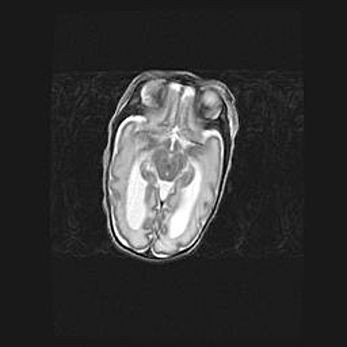

Мальформация Денди-Уокера. Киста задней черепной ямки.

Агенезия мозолистого тела.

Возраст: 2,5 месяца

Вес: 2420 г

Пол: женский

Окружность головы: 37 см

Срок гестации: 32 недели

Мальформация Денди—Уокера — редкий вид патологии ЦНС, представляющий собой врожденный порок развития каудального отдела ствола и червя мозжечка, ведущий к неполному раскрытию срединной (Мажанди) и латеральных (Лушка) апертур IV желудочка мозга. Для этогно синдрома характерна триада симптомов: гипотрофия червя мозжечка и/или полушарий мозжечка, кисты задней черепной ямки, гидроцефалия различной степени. В 70% случаев порок сочетается и с другими аномалиями головного мозга, в частности с агенезией мозолистого тела.